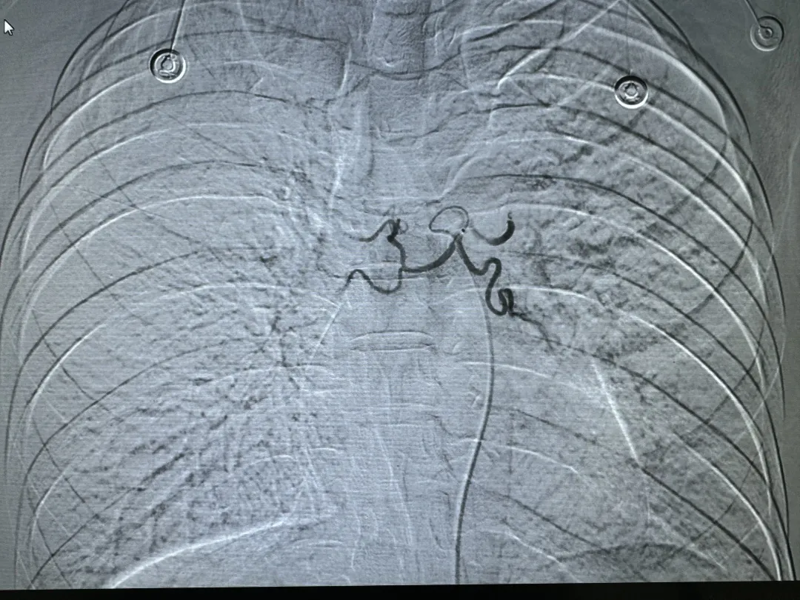

介入手术后,无出血

经导管支气管动脉栓塞止血术是一项高难度的手术,需要医生精确地定位出血口,在极小的、错综复杂的血管里,巧妙的把材料封堵住血管出血口,才能确保手术的成功。在这次手术中,多学科的医务人员紧密配合,各展所长,充分发挥各自的专业技能,成功抢救了患者生命。